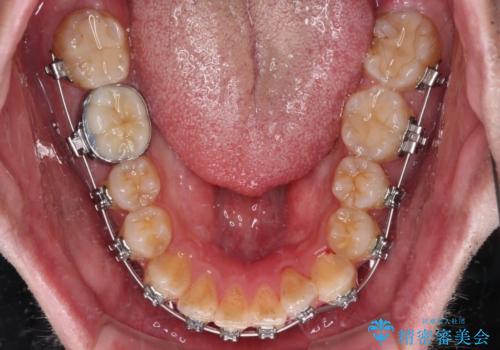

- 矯正装置

- メタルブラケット

- 治療期間

- 9ヶ月